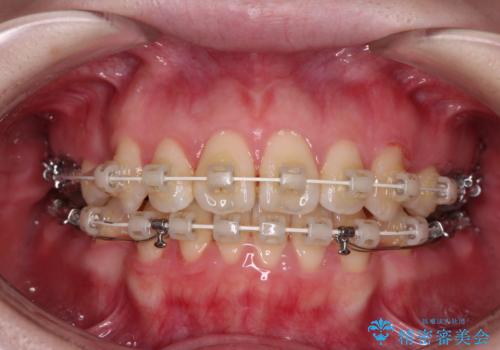

- 審美装置

- 2年9ヶ月

- 30回以上

強い舌の突出癖により、上下前歯が前方に飛び出しており、特に上顎前歯は下顎よりも更に前方に位置している状態でした。

上顎前歯をしっかりと後方に移動させるため、口蓋側にアンカースクリューと補助装置を併用し、上下左右の第一小臼歯4本を抜歯し、ワイヤー装置にて矯正治療を行うこととしました。